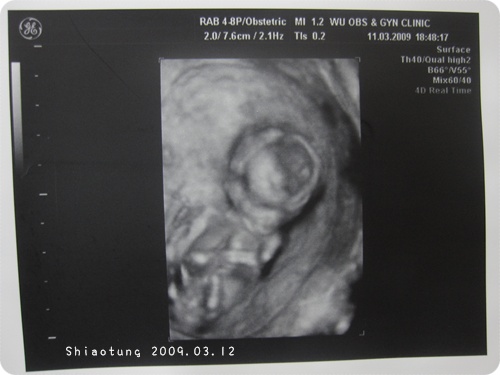

4D部分會在2分40秒以後才開始,

請耐心等待!!

但是我個人也看不出所以然,

反倒是4D以後的畫面有擷取下來,

就下面的照片,

看看就好滿足好奇心。

沒當過娘的就欣賞一下,

剛娘的就懷念一下!